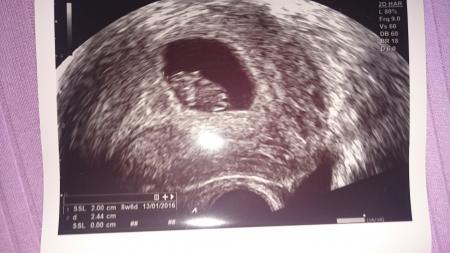

Herzlichen Glückwunsch erst mal :)) Ich war heute auch dort das kleine ist jetzt schon 2,0 cm groß :)

Bild zu